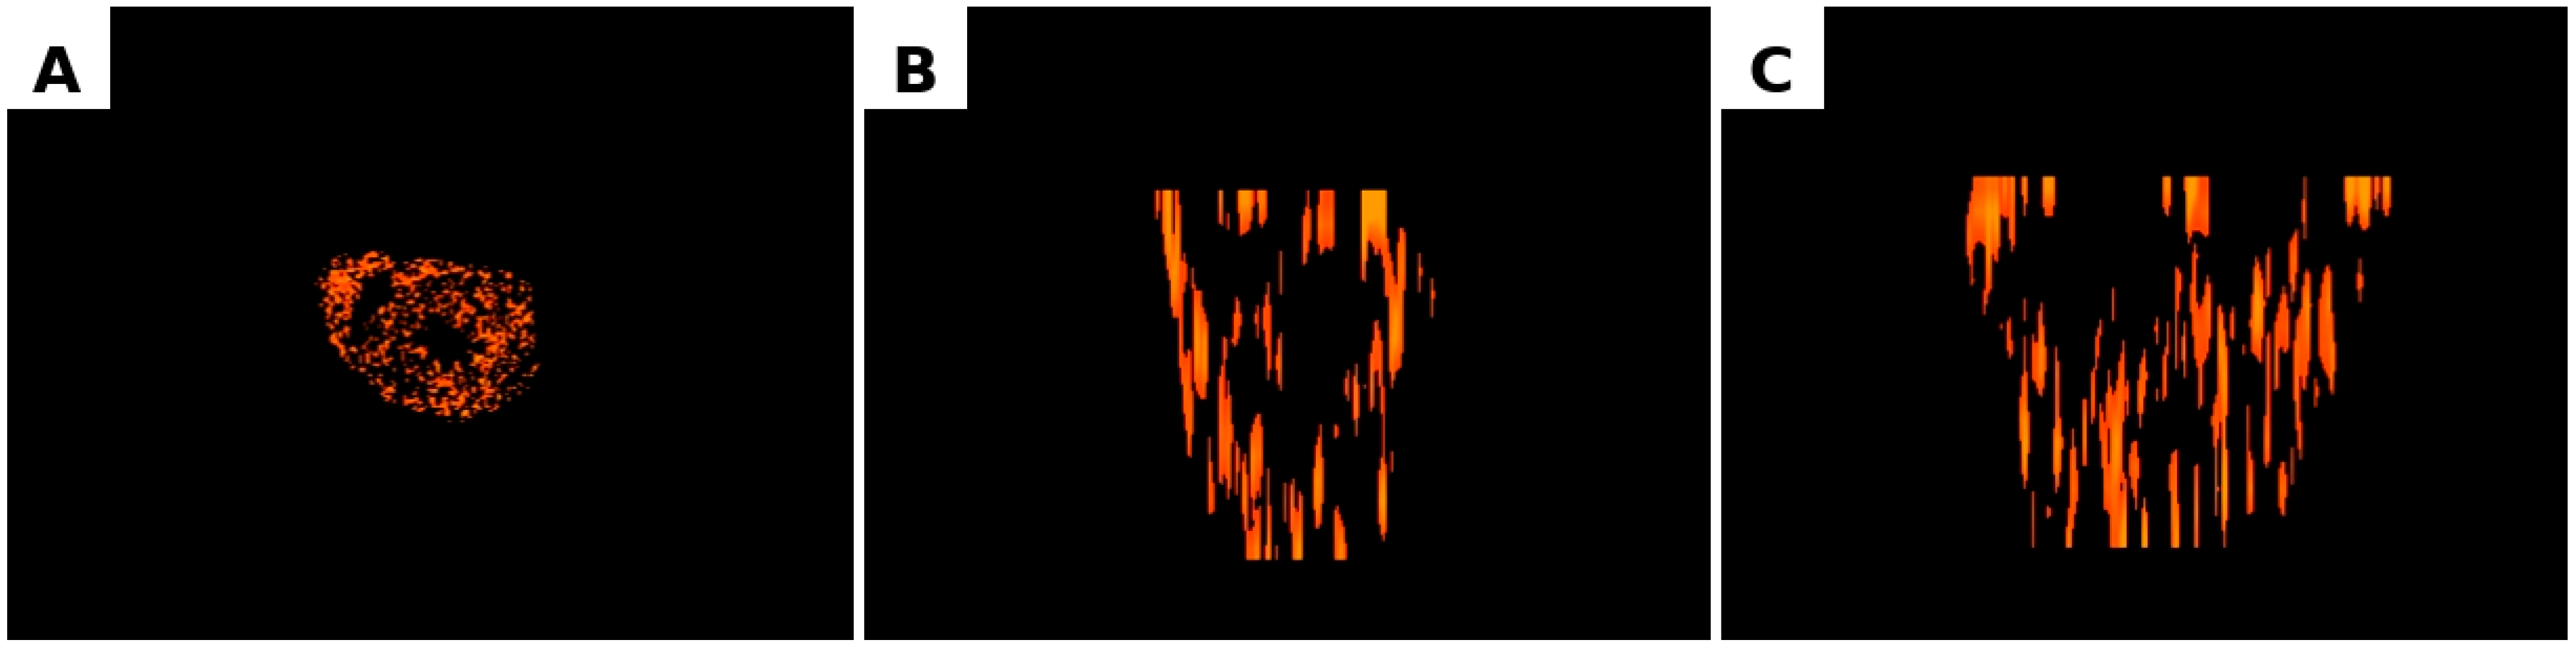

Figure 7. Three-dimensional reconstruction of ventricular myocardial innervation. (A) Axial (Z), (B) Coronal (Y), (C) Sagittal (X). Projection of the reconstructed three-dimensional model showing the spatial distribution of nerve fibre density within the ventricular myocardium following integration of histological density maps with MRI data.

The atrioventricular (AV) groove exhibited the highest degree of spatial heterogeneity of innervation. Entropy reached 1.52, the maximum value among all analysed sections. Despite this heterogeneity, Moran’s I remained relatively high (0.80), indicating that clustering of nerve fibres was still present but organised in a more complex spatial configuration. The hotspot volume in this region was 3.40 million pixels, which was lower than in the mid- and upper-ventricular regions but higher than in the apical area. This distribution likely reflects the presence of large nerve trunks and ganglionated plexuses in the region of the atrioventricular groove (Figure 5 and Figure 6). The constructed 3D animation of rotation can be found in the Supplementary Materials to the article. The main plane sections are available in Figure 7.